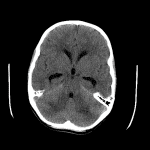

- CT

- Patchy hypoattenuation in the bilateral cerebellar hemispheres with mass effect in the posterior fossa resulting in crowding of the fourth ventricle and inferior descent of the cerebellar tonsils into the foramen magnum

- Enlargement of the lateral and third ventricles with mild rounding of the temporal horns and mild subependymal edema